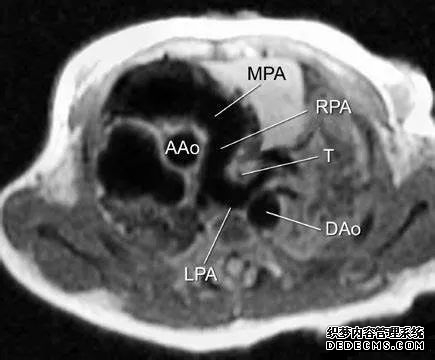

6、MRI 作为无创检查方法均能准确显示血管和气道、血管环和吊带的异常。MRI 虽无电离辐射,但因扫描时间长,镇静要求高,尤其对于存在呼吸窘迫患儿,过度镇静不安全,因此不适合临床症状严重者。